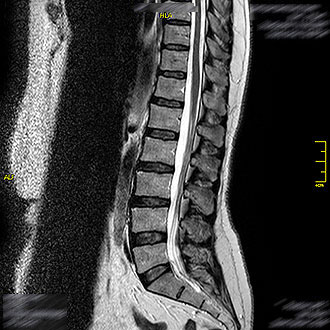

Im Kernspin Zentrum Köln werden alle Abschnitte der Wirbelsäule – Hals-, Brust-, Lenden- sowie Kreuzbeinregion – mit modernster Magnetresonanztomographie untersucht.

Die MRT bietet eine strahlungsfreie und hochauflösende Darstellung von Bandscheiben, Wirbelkörpern, Nerven und dem Rückenmark.

Die MRT der Lendenwirbelsäule ist die am häufigsten durchgeführte Wirbelsäulenuntersuchung. Sie zeigt Bandscheibenvorfälle, Fehlstellungen, Tumoren, Entzündungen oder Fehlbildungen zuverlässig auf.

Im Kernspin Zentrum Köln wird sie oft bei Lumbalgie oder Lumboischialgie (Rücken- und Beinschmerzen) durchgeführt. Auch bei chronischen Rückenschmerzen oder Versteifungserkrankungen wie Morbus Bechterew liefert die MRT wichtige Erkenntnisse für die Behandlung.